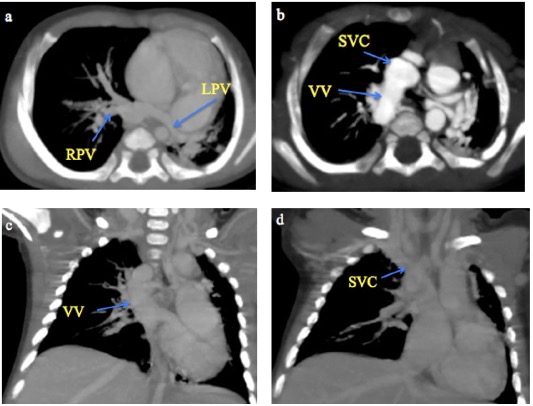

MDCT images of TAPVC are shown in Figures 4 and 5, demonstrating the characteristic drainage patterns of the supracardiac and infracardiac types, respectively.

Fig. 5 A month old male infant with infracardiac total anomalous pulmonary venous connection. a) CT Pulmonary angiography coronal MIP and b) 3-D volume-rendered CT images show the right and left superior and inferior pulmonary veins (RCPV and LCPV) joining to form a vertical vein (white arrow) that descends through the diaphragm and drains into a dilated and tortuous splenic vein (SV).

TAPVC, in which all four pulmonary veins drain into the systemic veins rather than the left atrium, is usually diagnosed on echocardiography4. However, MDCT angiography is indispensable when echocardiographic visualization is limited or complex CHD is suspected. The supracardiac type of TAPVC was the most common in this study (45.5%), consistent with previous reports (45%-55%)8,10. In our study, MDCT angiography effectively characterised various drainage patterns, including a supracardiac TAPVC draining into the SVC and a rare infracardiac type of TAPVC draining into the splenic vein, also reported by AI Mutari et al26. MDCT’s 3D reconstructions provided crucial details for accurate delineation of venous stenosis.